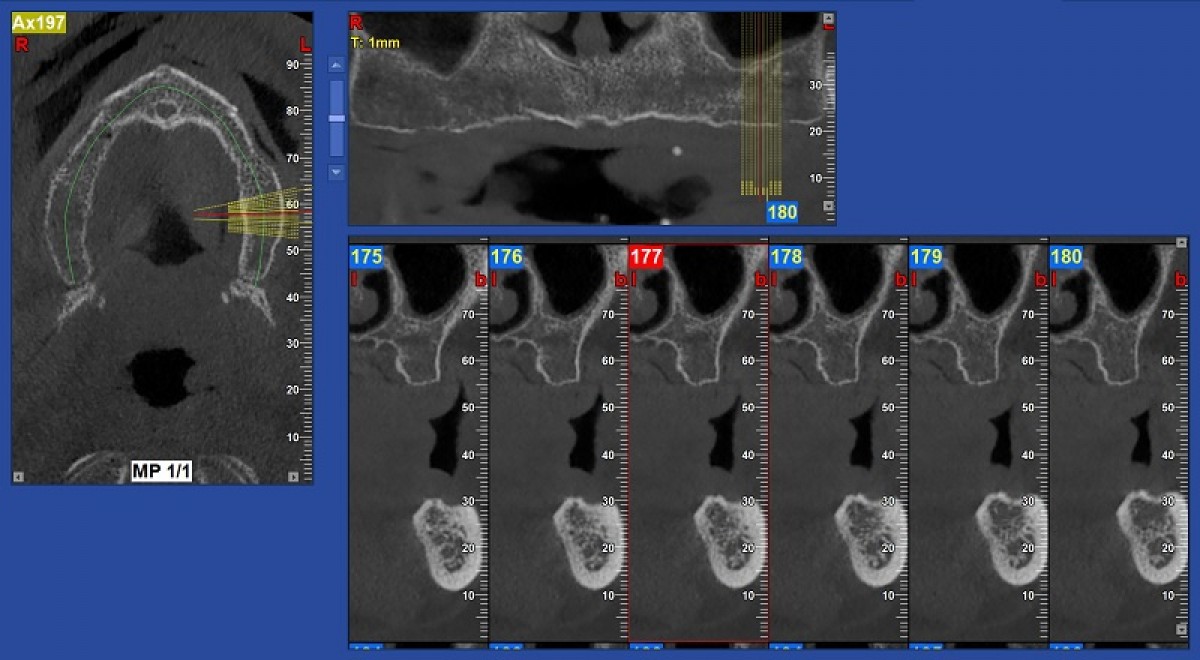

In this particular case, the computerized cephalometric analysis performed using the Nemoceph (Nemotec) software, highlighted on the lateral projection a skeletal class 1, a brachyfacial type and pathological positioning of the upper and lower incisors; the latter appeared retro-positioned compared to their respective skeletal bases (incisive overbite) and linguo-inclined (insufficient torque). This situation gave rise to the so-called "incisor wall" which could compromise correct occlusal contact and proper functioning of the temporomandibular joints. It also influences the aesthetics of the smile. Cephalometric analysis on the frontal plane showed a good transverse relationship between the upper and lower jaws and confirmed the rightward deviation of the lower midline. To plan the orthodontic treatment, we performed a cephalometric VTO to simulate the correct positions that the incisors should reach at the end of the course of treatment (fig. 5).

The cephalometric VTO allowed us to identify the exact movements the incisors need to make in the sagittal and vertical planes. To complete the three-dimensional treatment planning, the virtual set-up was used. The dental arches were further scanned using the Trios (3Shape) scanner (fig. 6).